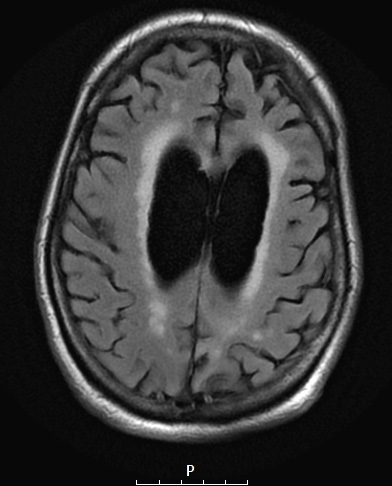

11A1-3 These axial FLAIR images demonstrate marked ventricular dilatation and substantial frontal, temporal (and parietal) lobe atrophy.